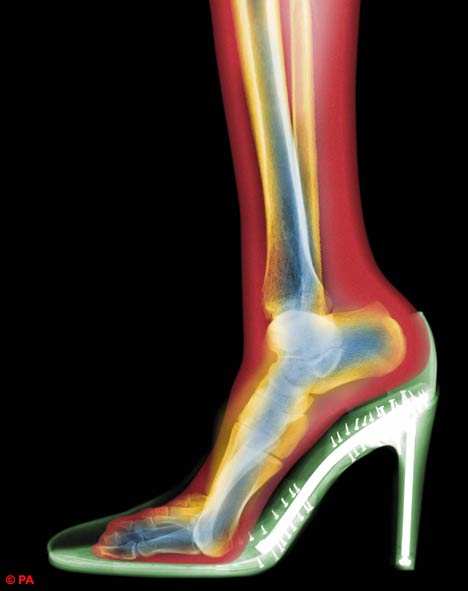

X-RAY